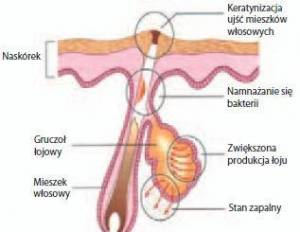

Trądzik pospolity to najczęstsza choroba gruczołów łojowych, związana przede wszystkim z nadprodukcją łoju.

Trądzik pospolity to najczęstsza choroba gruczołów łojowych, związana przede wszystkim z nadprodukcją łoju.